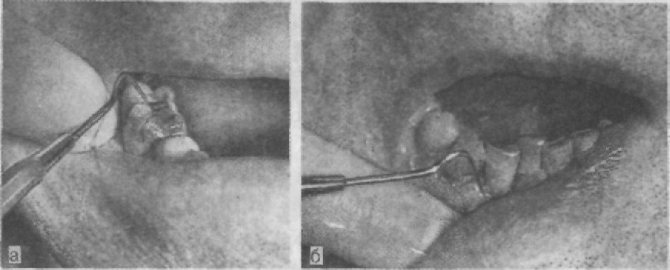

Процедура закритого кюретажу

Мета процедури – видалити грануляції і відкладення в зубних кишенях. Даний вид лікування виконується при невеликому ступені захворювання, якщо глибина пародонтальної кишені не більше 3 мм. Цілісність ясна при цьому не порушується, тому основний процес проходить наосліп.

Закритий кюретаж передбачає виконання таких дій:

- Антисептична обробка порожнини рота.

- Знеболювання потрібної області.

- Видалення відкладень і потемніло цементу за допомогою спеціальних інструментів.

- Частка вмісту пародонтальних кишень.

- Ретельна обробка кишені із застосуванням антисептиків і кровоспинних засобів.

- Накладення захисної пов’язки.

Протягом подальших декількох днів пацієнтові рекомендується уникати вживання твердої їжі. Проявляти обережність слід також при чищенні зубів, особливо в ділянці проведення процедури.